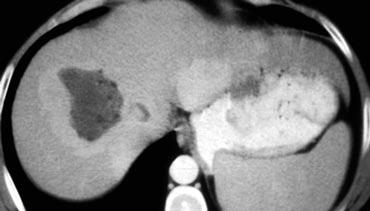

Tổn thương bên trái có các đặc điểm sau:

- Tổn thương giảm tỷ trọng ở thì động mạch và thì tĩnh mạch cửa, với ngấm thuốc ngoại vi.

- Tổn thương tăng tỷ trọng ở thì cân bằng, gợi ý mô xơ đặc.

- Tổn thương gây co rút bao gan.

Hình ảnh một khối thâm nhiễm kèm co rút bao gan và ngấm thuốc muộn kéo dài là đặc trưng điển hình của ung thư đường mật.

Ung thư đường mật thể thâm nhiễm không gây hiệu ứng choán chỗ, vì khi mô đệm trưởng thành, mô xơ sẽ co lại và gây co rút bao gan.

Không có nhiều loại u gây co rút bao gan, vì hầu hết các khối u thường gây phồng lồi bao gan.

Loại u phổ biến nhất gây co rút bao gan ngoài ung thư đường mật là ung thư vú di căn.